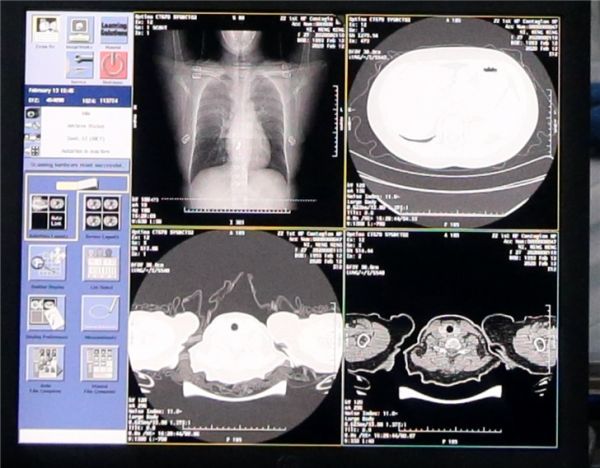

2月14日消息,在钟南山院士的指导下“快速检测试剂盒”成功诞生,据介绍这一测试盒可以在15分钟内得出结果,相比核酸测试分析时间大大提高。实际上,除了各类测试盒检测外,通过观察患者肺部CT图像的变化临床医生也能判断出患者是否感染了新冠肺炎,但是也存在一些问题。

一名患者的肺部CT图像数量高达300张,光凭肉眼的观察、对比的话,一次诊断需要耗费医生5分钟到15分钟不等的时间,效率并不算高。

针对这一难题,科技圈再度传来好消息。由阿里达摩院研发的AI诊断技术能够在20秒内对患者的肺部CT图像作出分析和判读,从而为临床医生提供确诊判断依据,准确率可以达到96%以上。

在AI技术的帮助下,现在20秒就能得出诊断结论,而这些数据也能为临床医生提供更多的参考。例如,病人肺部病灶的占比比例、病症的轻重程度等数据也能在诊断结果中显示,对临床医生来说这些信息足以帮助他快速地制定治疗措施。